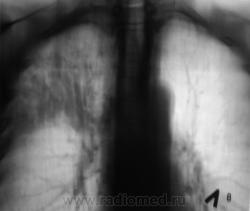

Произведена рентгенограмма в прямой стандартной проекции и томограммы в стандартных срезах.

«Пневмония», сразу показалась какой-то «фердиперсовой», с учетом лечения в стационаре ранее, довольно хорошего самочувствия пациента и наличием весьма «убогой» клиники. После проведения исследования было рекомендовано провести противовоспалительное лечение, исследование мокроты с целью проведения дифференциальной диагностики, рекомендована консультация фтизиатра.

Мы в протоколе, конечно, отметили, о возможности инфильтративного туберкулёза, д/д ряд даже не дали.

Пациент 4 месяца, по полной программе отлежал в областной конторе, ЦВК утвердило «инфильтративный». После выписки был направлен под надзор фтизиатра по месту жительства. Ниже иллюстрации после выписки.

Снимки сегодня.